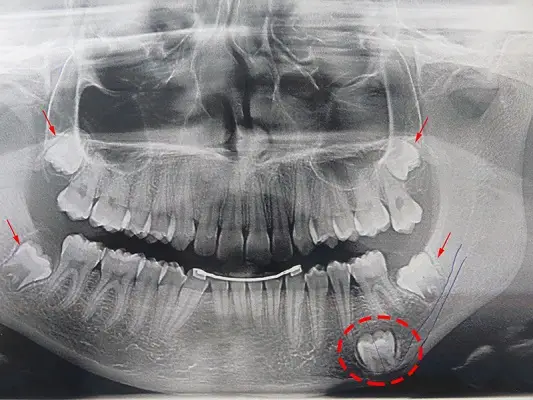

دندان نهفته، دندانی است که به درستی در دهان رشد نمی‌کند، اغلب به این دلیل که توسط استخوان، بافت لثه یا دندان دیگری مسدود شده است. شایع‌ترین دندان‌های نهفته، دندان‌های عقل (دندان‌های آسیای سوم) هستند که معمولاً بین ۱۷ تا ۲۵ سالگی ظاهر می‌شوند. وقتی این دندان‌ها گیر می‌کنند، می‌توانند باعث موارد زیر شوند:

دندان نهفته